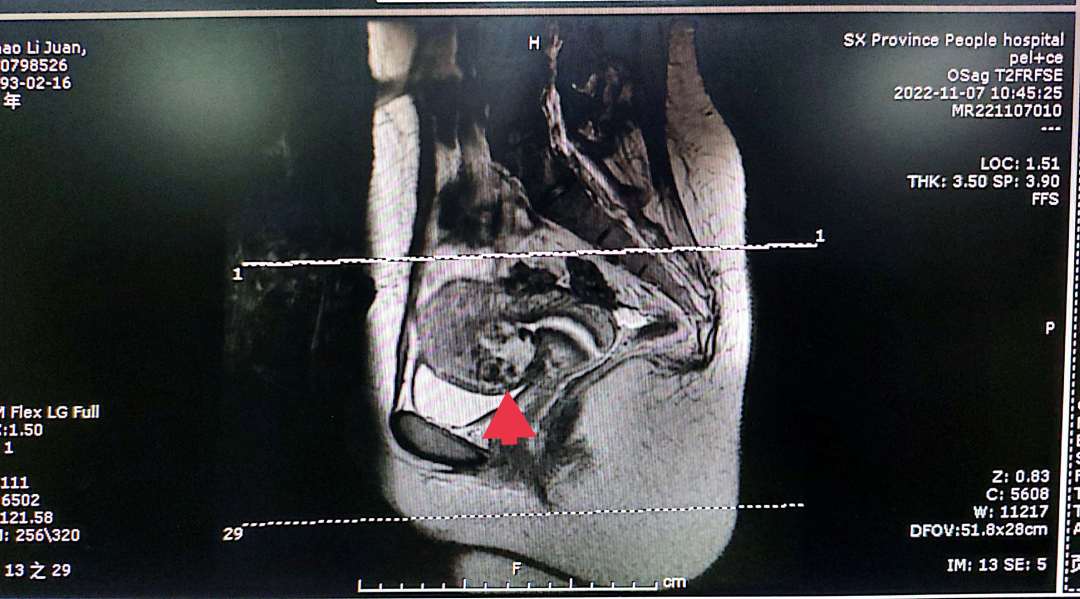

编者按 剖宫产瘢痕妊娠,是指受精卵在子宫切口上着床,在临床上这种情况要引起高度的重视,会随着妊娠囊的增大,造成局部的破裂,后果非常严重。本期【病例分析室】由山西省人民医院主任医师王素琴为大家分享一例剖宫产瘢痕部位妊娠(药流后)合并动静脉瘘,对于此情形,她是如何进行诊断和治疗的,详见以下病例分析。 病例介绍 患者29岁,主因“药流后2月,发现瘢痕妊娠4天”入院。 现病史:停经40天于当地医院行药流术,术后20天盆腔彩超未见异常。术后2月因“月经未复潮”就诊于我院,行盆腔彩超提示:瘢痕妊娠III型,动静脉瘘不除外。考虑“瘢痕妊娠”入住我科。血HCG:229.56mIu/mL。追问病史:药流术后未同房。 既往史:2009年、2021年于当地医院行剖宫产术。 婚育史:G4P2。 月经史:平素月经规律,5/25天,LMP:2022-07-01。 妇科检查:外阴正常,已婚未产型;阴道通畅,可见少许分泌物;宫颈光滑,前穹隆呈紫蓝色,触血阴性;宫体前位,大小约7*6cm大小,表面光滑,活动好,无压痛;双附件区未见明显异常。 辅助检查: 1)盆腔彩超: 子宫前壁下段瘢痕处可见44.4*34.3mm混合回声包块,向膀胱隆起,包块与膀胱间肌层变薄,厚约0.7mm,CDFI:包块内部及周边可见极丰富血流信号,可探及动静脉血流谱。考虑子宫前壁下段瘢痕处混合回声包块(瘢痕妊娠III型,动静脉瘘不除外)。 2)盆腔核磁: 子宫前壁下段瘢痕处及宫腔内见团块状异常信号影;病变周缘伴粗大迂曲血管。 3)血HCG:229.56mIu/mL。 术前诊断:剖宫产部位瘢痕妊娠III型(药流后)动静脉瘘?